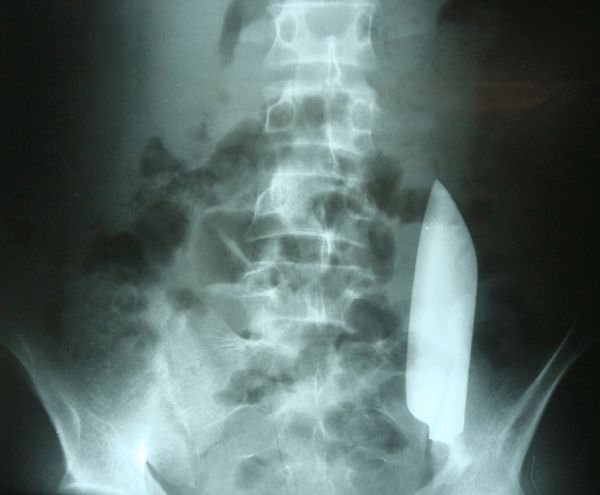

五、肚里藏刀

一位22岁的尼泊尔男子因为左下腹持续轻微疼痛来到急诊室。乍一看他似乎并无大碍,但通过X光片检查,医生发现了不同寻常的情况:他的肚子里藏着15厘米长的金属刀刃[5]。

肚子里进了一把刀?| Anamika Nepal, Ashish P. Rajbhandari

原来,就在此前一天,这名男子刚刚被人用这把刀刺伤。当时的急救者缝合了伤口,但不知为何却没有进行仔细检查,结果把从刀柄上脱落的刀刃一并缝进了他的肚子里。这把刀从男子的右侧肋部刺入,但它一天后却自己跑到了左下腹位置,游走途中奇迹般地没有造成任何内脏损伤。最终,医生进行手术,把这把在肚子里乱跑的刀取了出来。